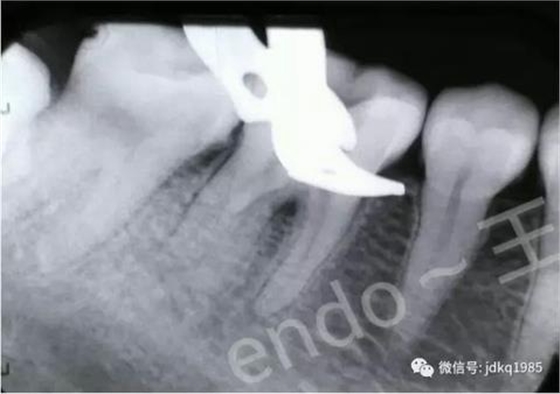

術(shù)前X線片可見近中根管內(nèi)分離器械

術(shù)后X線片,確認(rèn)近中根管內(nèi)分離器械已成功清理